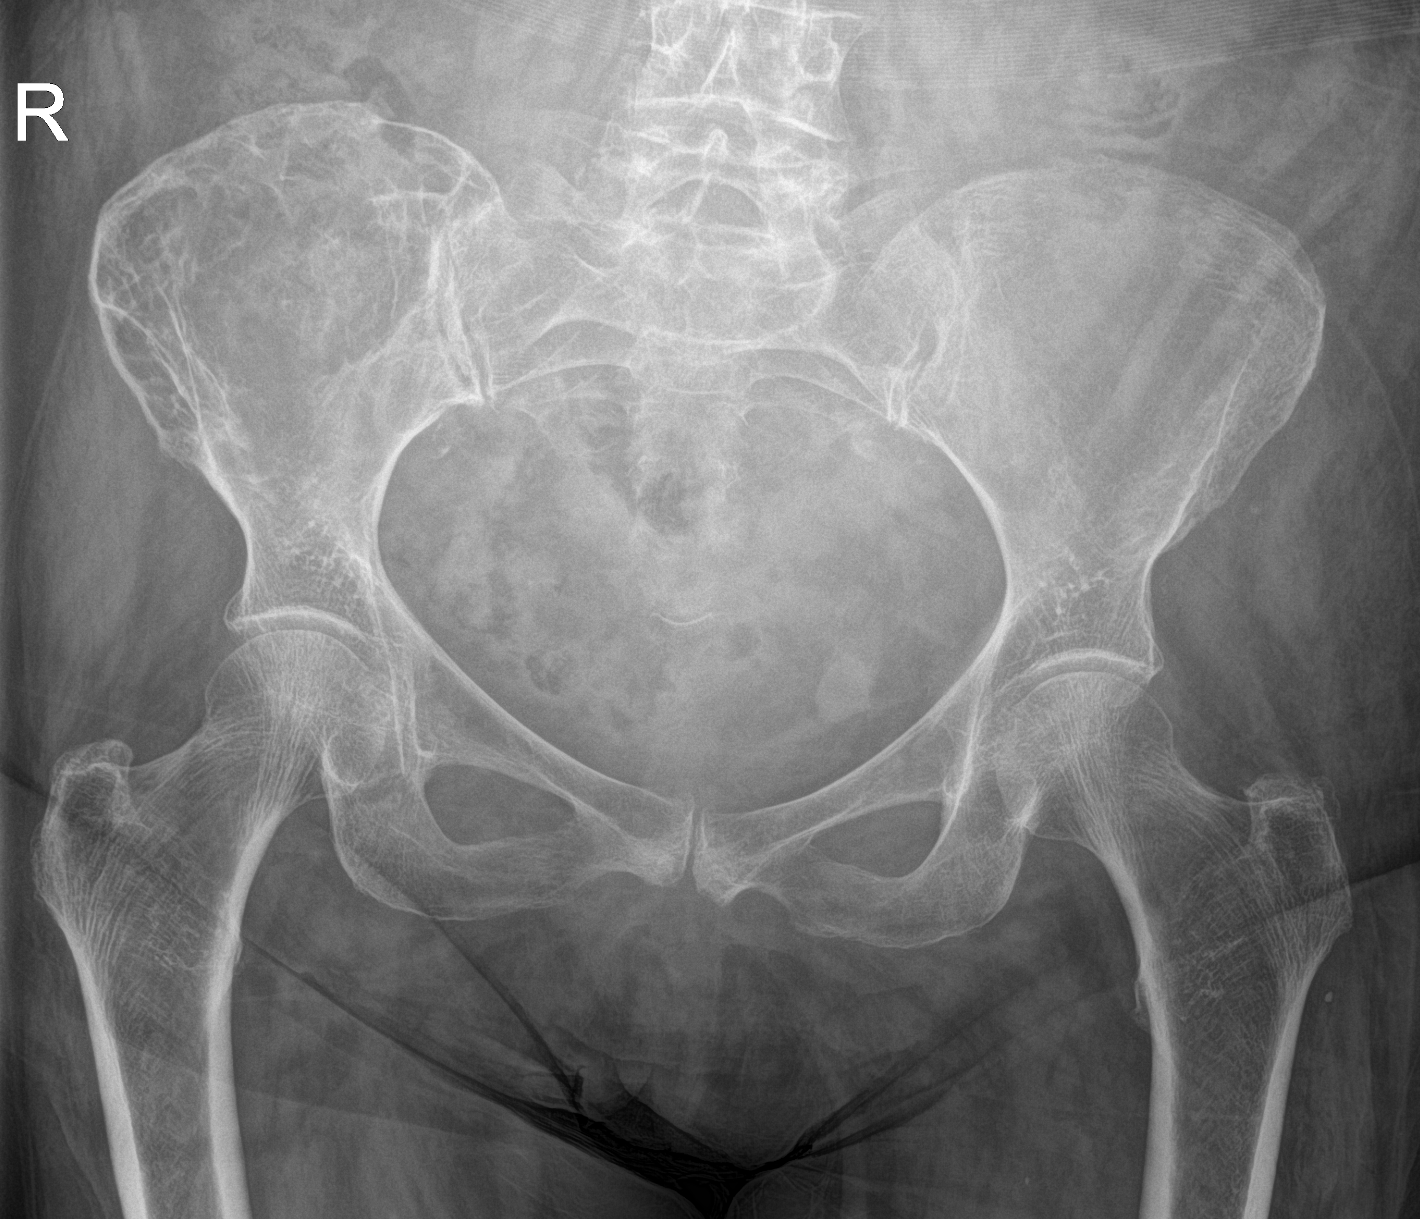

3. Paget's disease, right iliac wing